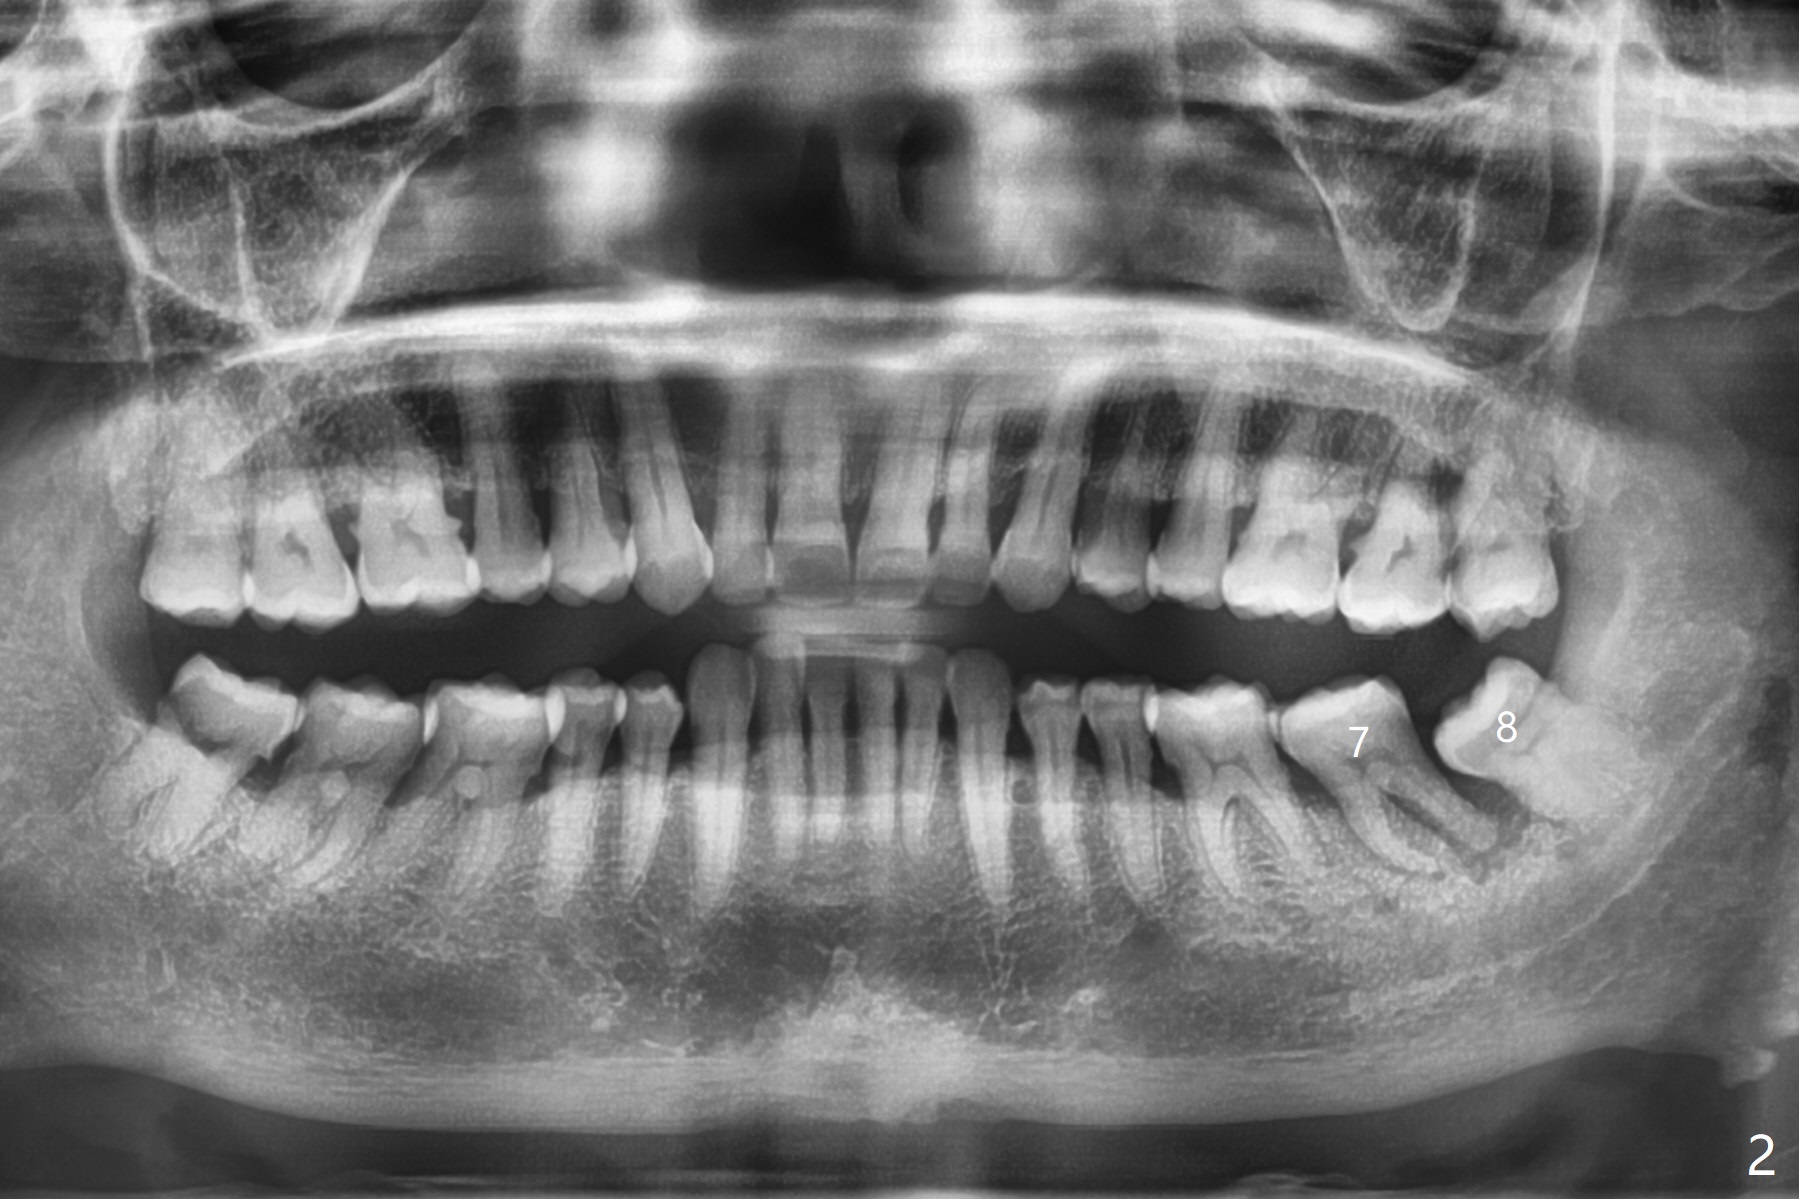

65岁女,南方人(广州),主诉左下肿胀,8舌侧粘膜穿孔(图一(舌侧观):<),初步问诊,回答:“全身没问题”,详细问诊:骨质疏松,静脉注射Reclast两年,准备拔除使用PRF修复缺损,全景片显示7远中骨质吸收严重(图二),因此8拔出后,牙槽窝塞入胶原塞(图五:C),将粘性骨粉放置7近中,远中(图五:白*)以及颊侧(黑*),把一片PRF膜覆盖骨粉(7颊侧,8牙槽窝口),另外一片放置于8舌侧穿孔(图四:箭头)颊侧,促进愈合,然后使用4-0 PGA缝合(图三(颊侧观),图四(舌侧观))。术后5天用钢丝(图六:*)和树脂固定松动牙,并且降低咬合。舌侧穿孔正在愈合(图七:>)。虽然术后三周智齿伤口裂开,但是没有症状,病人满意第二磨牙不再松动(图八),开始深洗。下次复诊拍摄根尖片观察骨质愈合。术后二个月第二磨牙远中没有骨质再生(图九),临床上远中牙根暴露。